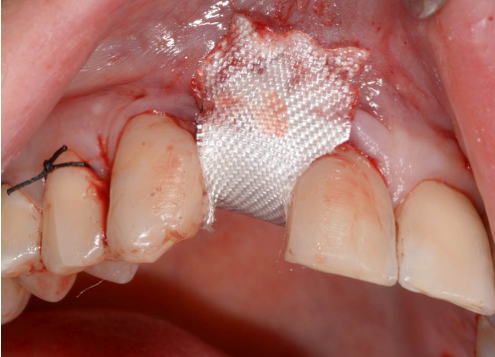

Während oder nach oralen Operationen, von der Extraktion von Zähnen bis hin zu rekonstruktiven Eingriffen, oder Implantationen, bietet BloodSTOP® iX eine schnelle und vorübergehende Kontrolle von Oberflächenblutungen.

BloodSTOP® iX absorbiert schnell Blut und verwandelt sich in ein klares Gel, um die Wunde mit einer transparenten Schutzschicht zu versiegeln, Blutplättchen zu binden und zu aktivieren, sowie die Gerinnung und Wundheilung zu unterstützen.

Anwendungsbeispiele

- Wundversorgung nach Entnahme von Weichgewebstransplantaten